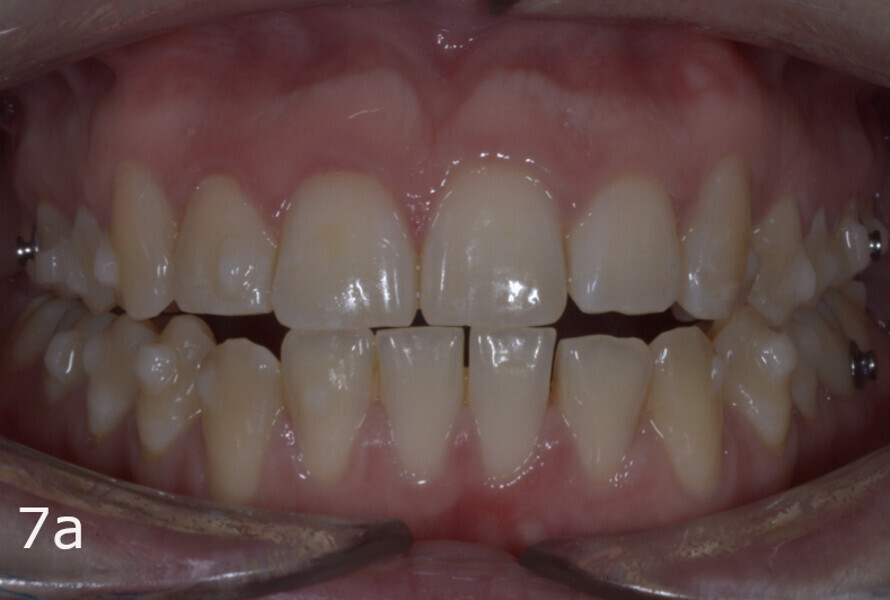

The treatment objectives included closing the anterior open bite, achieving a bilateral Angle Class I relationship and a proper overjet and overbite, correcting the midline discrepancies, and achieving a profile harmonisation. The treatment plan consisted of orthodontic camouflage treatment with asymmetric distalisation in three of the four quadrants using Invisalign aligners (Align Technology) and third molar extraction. The Invisalign Comprehensive package was chosen, and 63 pairs of aligners were used (Figs. 7–10). Each aligner was worn for 20 hours a day for one week each. The use of Class III elastics on both sides was indicated. Afterwards, ten refinement aligners were needed to improve the interdigitation on the right side (Figs. 11 & 12).